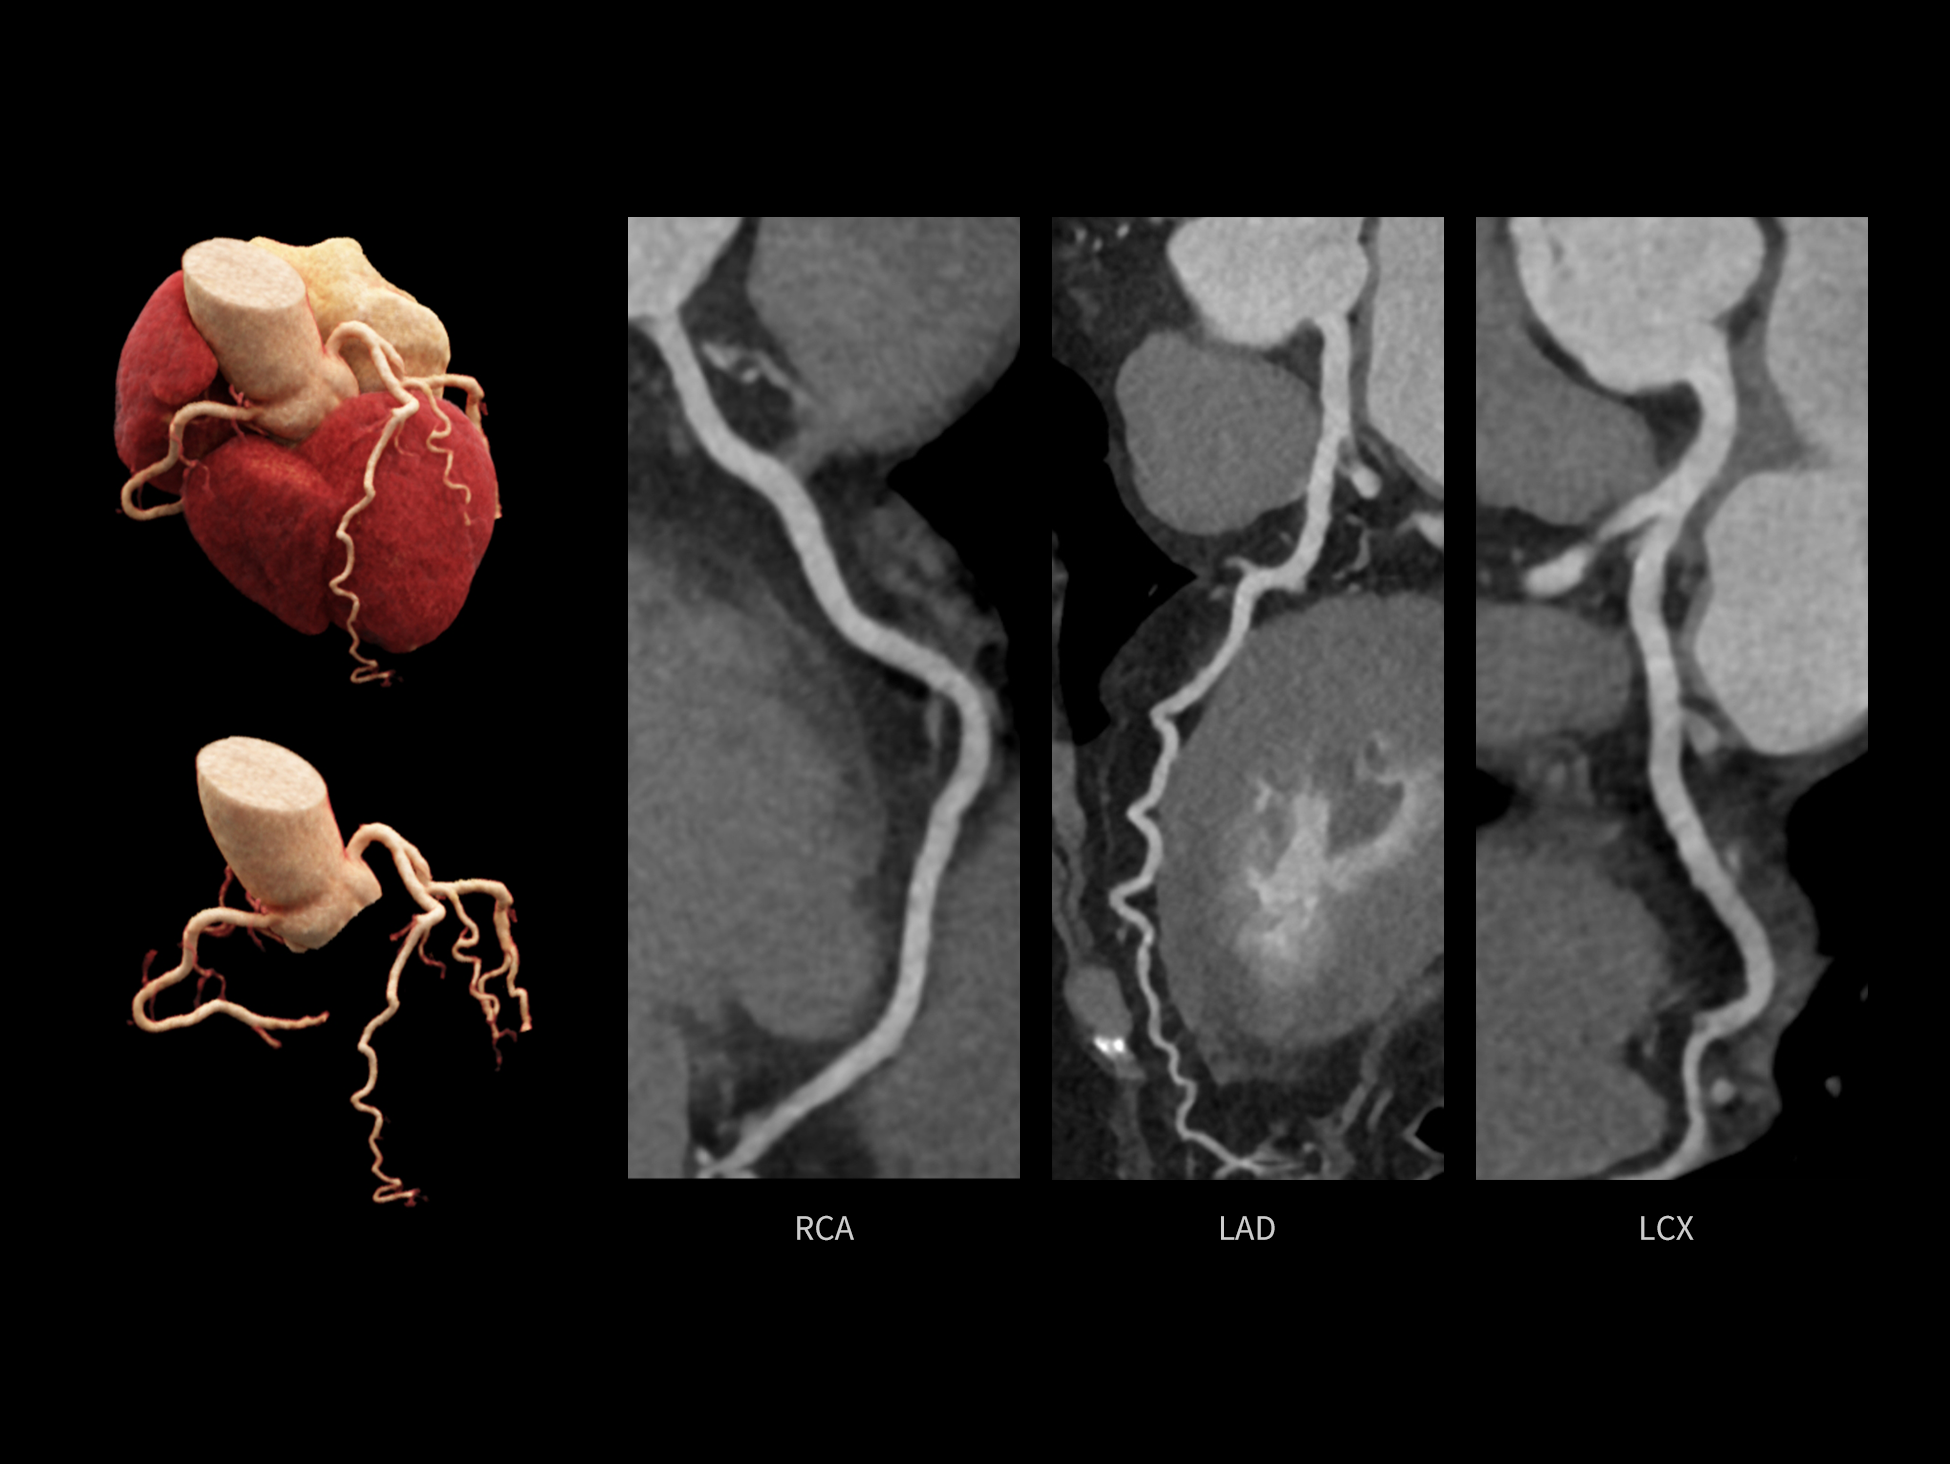

CardioCapture 2.0 通过“识别–追踪–建模–校正”的完整流程,精准分割心脏结构,动态追踪运动轨迹,并构建多时相运动场,最终实现冠脉、瓣膜、心肌及心室结构的同步校正,清晰洞见每一次心跳细微变化,真正将心脏动态掌握于毫秒之间。

CardioCapture 2.0 在目标时相前后重建多时相影像,通过深度学习网络精准提取冠脉中心线,进而建立时相间运动模型,实现对冠脉分段图像的精准运动校正。

冠脉运动校正